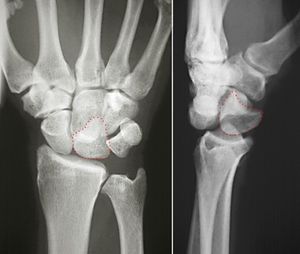

반달뼈는 손 안쪽에 위치한 초승달 모양의 손목뼈이다. 손목뼈의 몸쪽 열에 위치하며, 요골, 손배뼈, 세모뼈, 큰 뼈, 갈고리뼈와 연결된다. 손배뼈와 세모뼈에 부착된 인대, 요골의 반달뼈 오목 내 위치를 통해 안정화된다. 근위면은 요골과, 가쪽 면은 손배뼈와, 안쪽 면은 세모뼈와 관절을 이루며, 혈액 공급은 등쪽 및 손바닥쪽 가지에서 받는다. 모양과 혈액 공급 방식에 변이가 있으며, 뼈되기는 18개월에서 4년 3개월 사이에 시작된다. 손목의 움직임에 관여하며, 손목뼈 중 가장 흔하게 탈구된다. "초승달 모양"을 뜻하는 라틴어에서 유래되었으며, 양서류와 파충류에서는 중간골이라고 불린다. 유두골, 유구골, 요골, 주상골, 삼각골과 관절을 이룬다.

반달뼈는 손 안쪽에 위치한 초승달 모양의 손목뼈이다. 반달뼈는 손목뼈의 몸쪽 열에 위치한다. 몸쪽으로는 요골에 닿아있고, 가쪽으로는 손배뼈, 안쪽으로는 세모뼈, 먼쪽으로는 큰 뼈와 연결된다. 반달뼈는 또한 먼쪽과 안쪽 표면에서 갈고리뼈와도 연결된다.[2][5]반달뼈는 손배뼈에 부착된 안쪽 인대와 세모뼈에 부착된 가쪽 인대에 의해 안정화된다. 요골과 손목뼈 사이의 인대와 요골의 반달뼈 오목 내 위치 또한 반달뼈의 위치를 안정시키는 역할을 한다.[5]

반달뼈의 근위면은 매끄럽고 볼록하며, 요골과 관절을 이룬다. 가쪽 면은 평평하고 좁으며, 손배뼈와 관절을 이루는 초승달 모양의 면을 가지고 있다. 안쪽 면은 세모뼈와 관절을 이루는 매끄럽고 사각형의 면을 가지고 있다. 손바닥 면과 등쪽 면은 거칠다. 등쪽 면은 넓고 둥글다. 반달뼈의 원위면은 깊고 오목하다.[3]

반달뼈는 손목뼈 중에서 가장 흔하게 탈구되는 뼈이다.

반달뼈는 몸쪽으로는 요골에 닿아있고, 가쪽으로는 손배뼈, 안쪽으로는 세모뼈, 먼쪽으로는 큰 뼈와 연결된다. 반달뼈는 또한 먼쪽과 안쪽 표면에서 갈고리뼈와도 연결된다.[2]

반달뼈의 근위면은 매끄럽고 볼록하며, 요골과 관절을 이룬다. 가쪽 면은 평평하고 좁으며, 손배뼈와 관절을 이루는 초승달 모양의 면을 가지고 있다. 안쪽 면은 세모뼈와 관절을 이루는 매끄럽고 사각형의 면을 가지고 있다. 반달뼈의 원위면은 깊고 오목하다.[3]